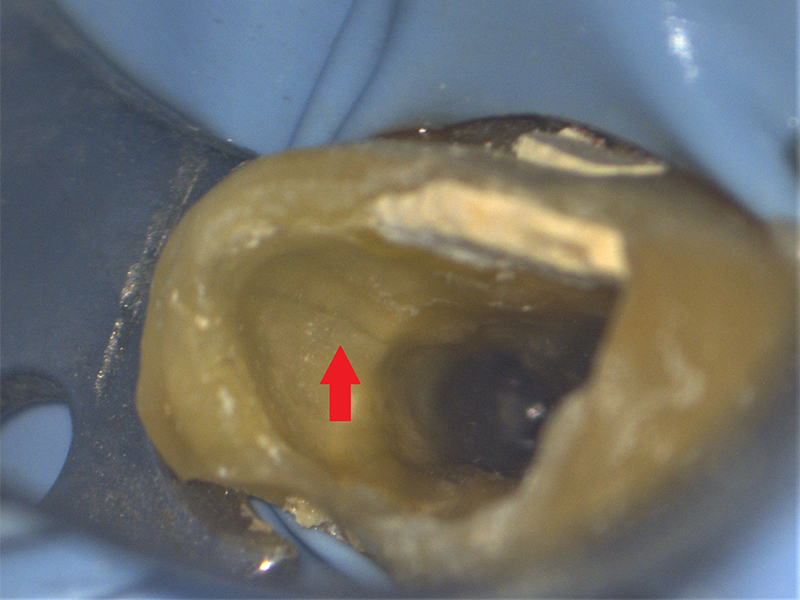

- 牙裂

以上的疾病,有的的確會行舒緩,但有的狀況卻不宜拖延。譬如:一時的蛀牙未處理、蛀牙深入到牙神經之後,就得進行根管治療了。又譬如牙醫師最頭疼的-「裂齒 (cracked tooth)」,裂齒的初期往往只是「咬起來一點酸酸的」;但根據錢醫師的個人經驗,「拖延超過一個月的裂齒」都極為嚴重、很多最後都是需要拔除的命運!

牙裂的鑑別診斷